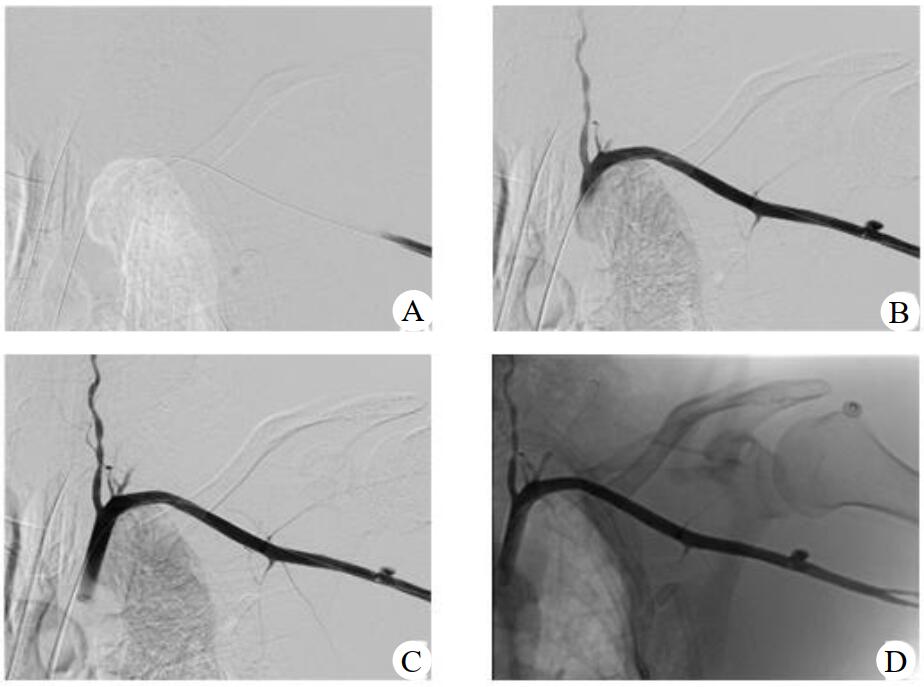

血管外科行左腋动脉造影和左腋动脉覆膜支架植入术,术中造影见左腋动脉破裂伴造影剂外渗,在三维路图引导下将带有导送装置的覆膜支架(8 mm×5 cm,GORE VIABAHN,美国)送入腋动脉,将支架中点覆盖血管破口后释放支架,再次造影见腋动脉通畅,无造影剂外渗,见图 2。

| A、B:左腋动脉造影可见造影剂外溢;C、D:置入覆膜支架后造影剂无外渗 图 2 左腋动脉造影和左腋动脉覆膜支架植入术 |

创伤性腋动脉破裂出血是一种临床少见、致死率高的肩部损伤,临床上发生率极低。腋动脉自身的创伤性损伤仅为主动脉损伤的2.9%~9%[1]。腋动脉损伤常常继发于上肢关节脱位,与下肢相比,其发生率不足1%[2]。因腋动脉位置隐匿,临床表现无明显特异性,易引起忽视。Kelley等[3]认为,当患者存在肩关节外伤史,动脉彩色多普勒超声检查发现存在动脉血流变化以及不断增大的腋窝肿块即可及时诊断腋动脉损伤。本病例血管造影可见左侧腋动脉起始部造影剂外渗,在置入覆膜支架后腋动脉显影通畅,无造影剂外溢现象,术后行三维重建可见支架影。